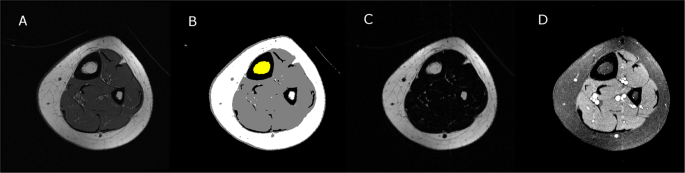

Total bone marrow volume was determined using the standard T1-weighted images and a custom program developed using Interactive Data Language (IDL; Research Systems, Inc., Boulder, CO). The procedure to determine bone marrow fat fraction (BMFFIDEAL) and bone fat marrow volume (BMFVIDEAL) using fat and water images generated from the IDEAL technique and the same custom program is briefly described in Fig. 1. The bone marrow was first identified using the T1-weighted images that were median filtered and separated from other tissues using a fuzzy-clustering algorithm. The T1 and IDEAL images were co-registered and the region (or mask) defined from the T1 images was applied to the corresponding fat and water images. The mean signal intensity (SI) was extracted from the fat and water images. BMFFIDEAL of each slice was calculated using the following equation24:

Visual description of the procedure to determine bone marrow fat fraction using fat and water images generated from the IDEAL technique and custom software. First, a raw T1-weighted magnetic resonance image (A) was filtered and then used to identify the bone marrow area (yellow region in B). The identified voxels were then applied to fat (C) and water (D) images to determine bone marrow fat area and to calculate bone marrow fat fraction. Bone marrow fat volume was quantified by accounting for the number of images, image thickness and spacing between images.

BMFFIDEAL was multiplied by the bone marrow area identified from T1-weighted images to estimate bone marrow fat area. The bone marrow fat volume for the midtibia was then calculated.